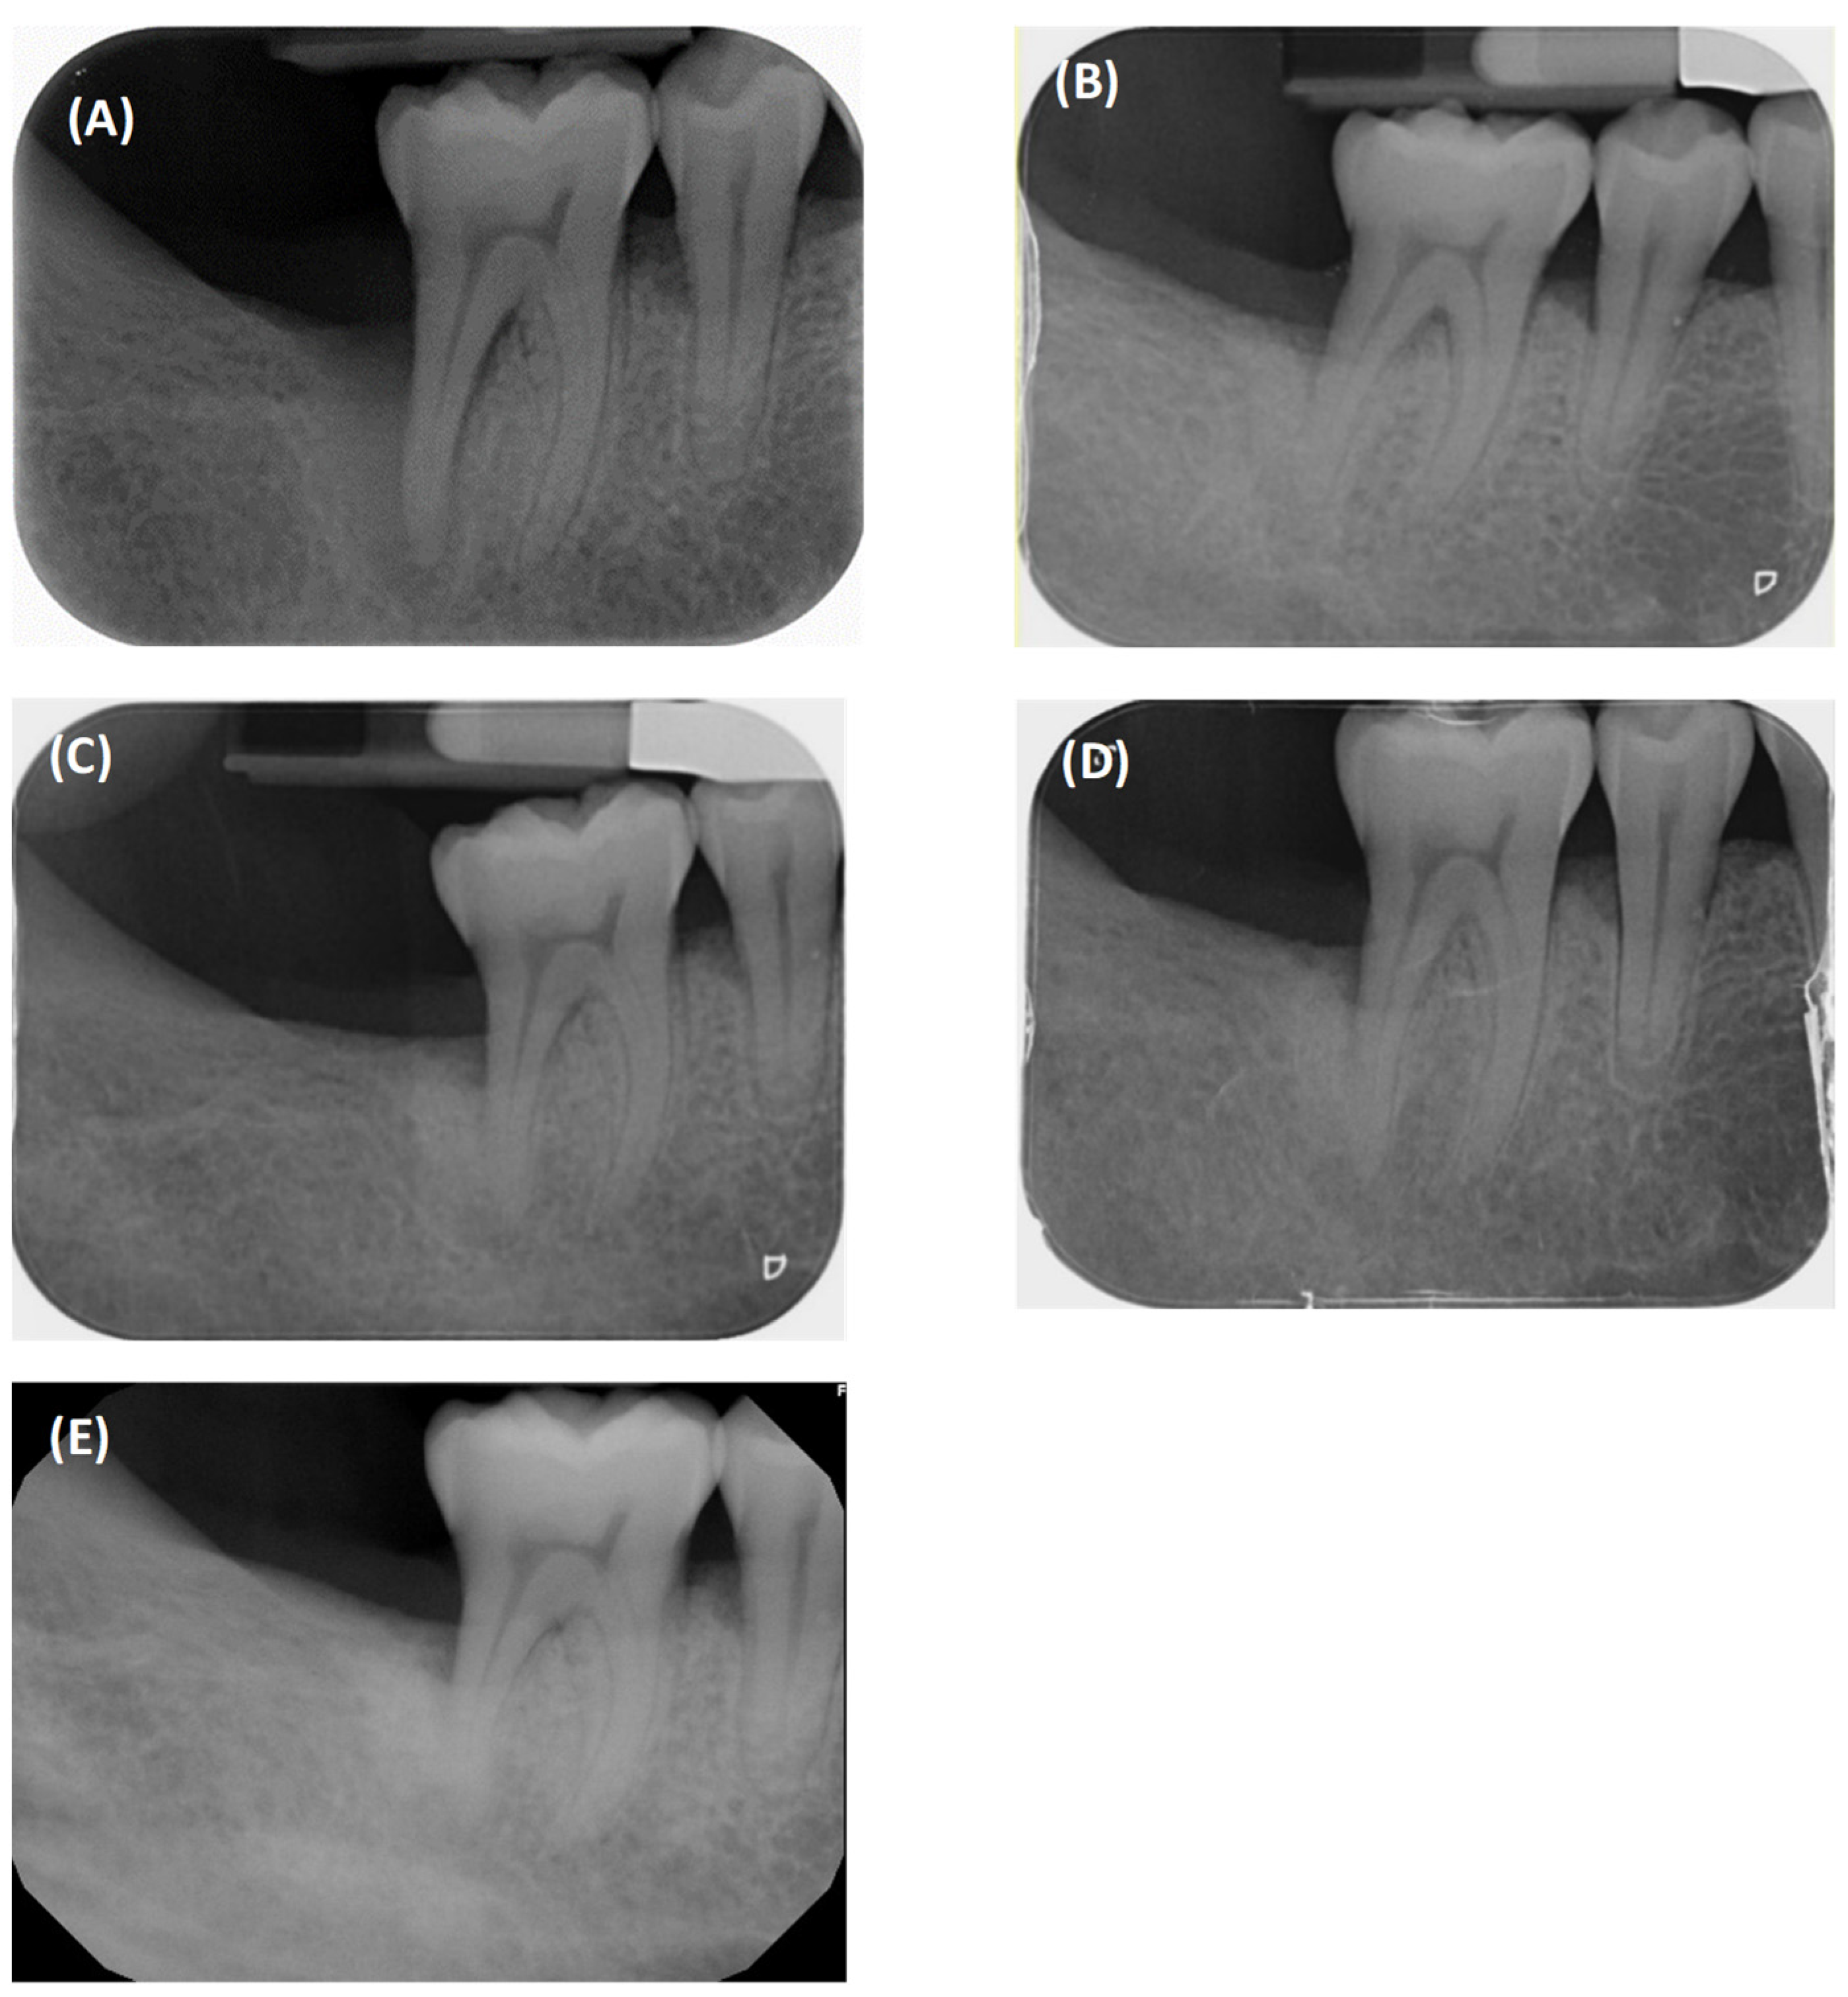

2.1. Case 1

2.2. Case 2

3. Results

| PPD (mm) | 11 | N/A | 4 | 4 | 3 | 3 | 3 | 3 | 4 |

| PPD reduction compared to baseline (mm) | N/A | N/A | −7 | −7 | −8 | −8 | −8 | −8 | −7 |

| CAL (mm) | 13 | N/A | 6 | 6 | 5 | 5 | 5 | 5 | 6 |

| CAL gain compared to baseline | N/A | N/A | +7 | +7 | +8 | +8 | +8 | +8 | +7 |

| BOP | + | N/A | − | + | − | − | + | − | + |

| GR (mm) | 2 | N/A | 2 | 2 | 2 | 2 | 2 | 2 | 2 |

| % bone fill | N/A | N/A | N/A | 73 | N/A | 73 | NA | 73 | 71 |

| PPD (mm) | 14 | N/A | 5 | 5 | 5 | 5 |

| PPD reduction compared to baseline (mm) | N/A | N/A | −9 | −9 | −9 | −9 |

| CAL (mm) | 16 | N/A | 8 | 8 | 8 | 8 |

| CAL gain compared to baseline | N/A | N/A | +8 | +8 | +8 | +8 |

| BOP | + | N/A | + | + | + | + |

| GR (mm) | 2 | N/A | 3 | 3 | 3 | 3 |

| % bone fill | N/A | N/A | 100 | 100 | 100 | 100 |